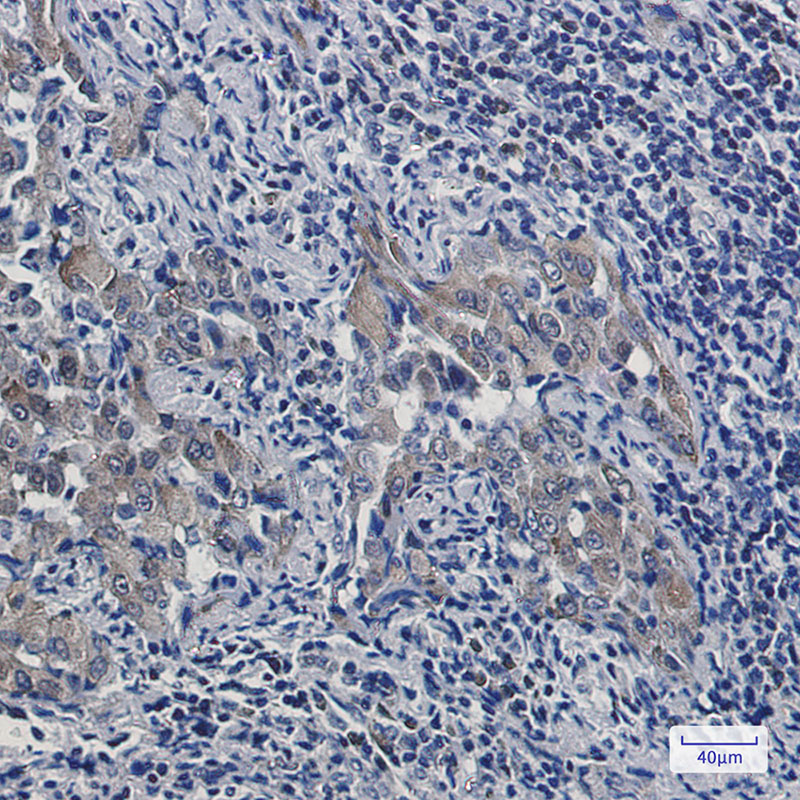

Immunohistochemistry analysis of paraffin-embedded Human colon cancer using alpha smooth muscle Actin antibody.High-pressure and temperature Sodium Citrate pH 6.0 was used for antigen retrieval.